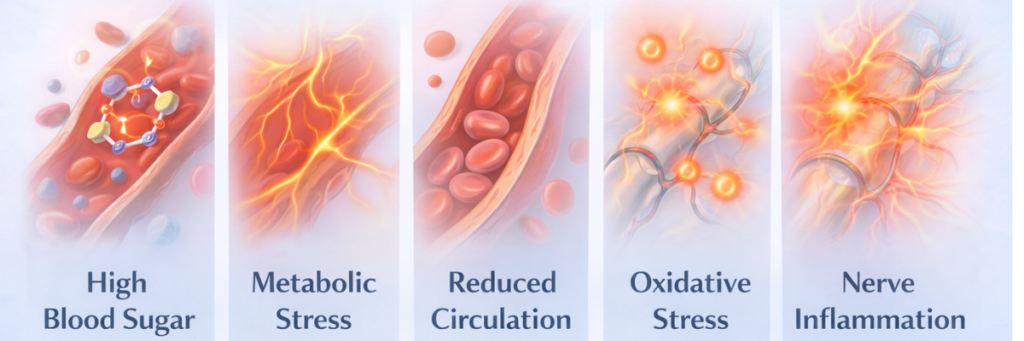

Possible Causes of Diabetic Neuropathy

Several biological factors may contribute to diabetic neuropathy. For instance, long-term metabolic stress may influence the small blood vessels that supply nutrients to nerve tissues. As a result, nerve cells may gradually receive less oxygen and fewer essential nutrients. Consequently, nerve signaling efficiency may slowly decline over time.

In addition, inflammation or oxidative stress may also affect the environment surrounding nerve fibers. Because of these influences, nerve signaling may gradually change. Consequently, communication between nerves and surrounding tissues may become less consistent.

Therefore, understanding the broader causes of nerve dysfunction may help explain how diabetic neuropathy develops over time.